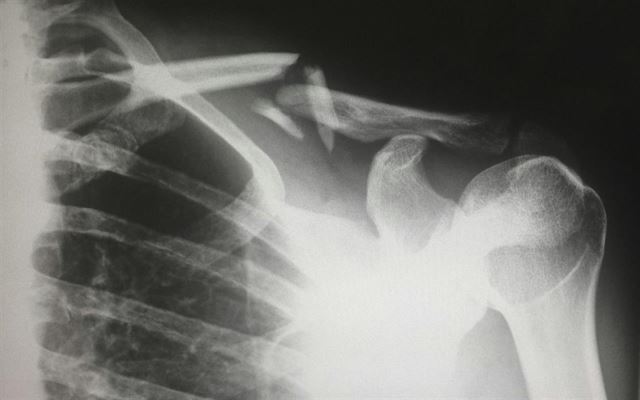

Impingement - Årsager og behandling

Skulder impingement , også kendt som indeklemningssyndrom, er en almindelig tilstand, der påvirker skulderens bevægelighed og kan forårsage betydelige smerter. Tilstanden opstår, når senerne i rotato